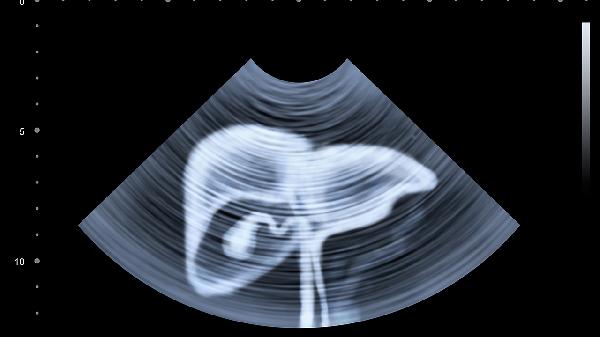

肝脏的代偿能力超强,等出现明显症状时,往往已经损失了70%以上的肝功能。建议脂肪肝患者每3-6个月复查超声和肝功能,40岁以上要加做甲胎蛋白检测。记住,今天对肝脏的每一分呵护,都是在为未来的健康储蓄。